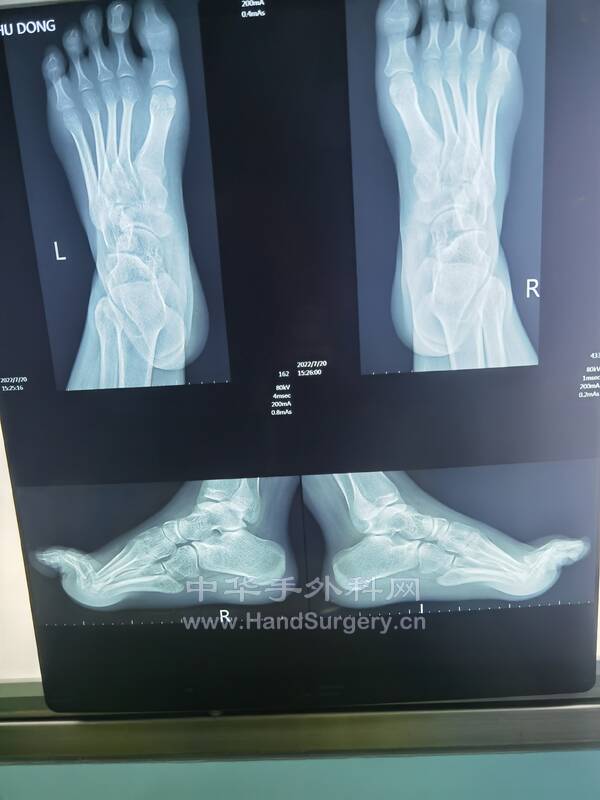

明日需要手术的右足马蹄外翻足,扁平足小患者资料(图18--41)

明日需要手术的右足马蹄外翻足,扁平足小患者资料(图1-24)